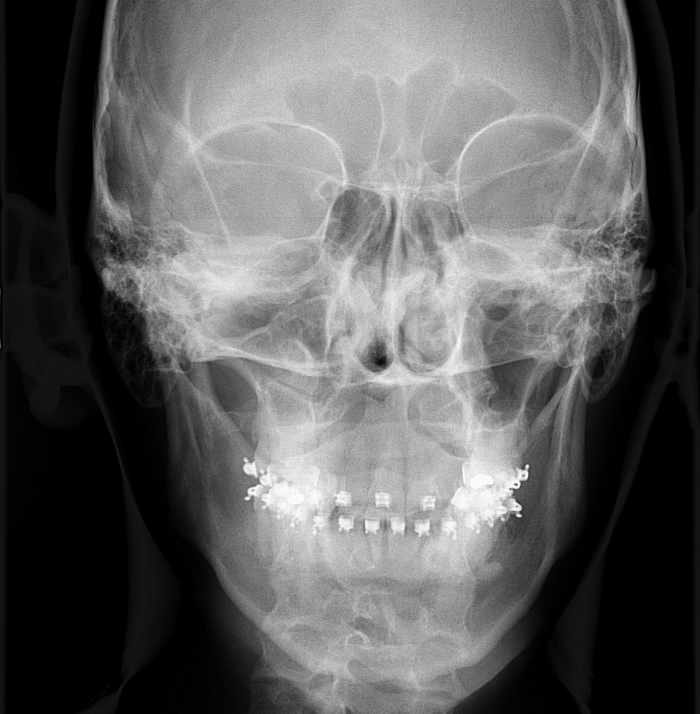

Telerradiografia frontal inicial - Clínica Cliniface

Telerradiografia frontal inicial